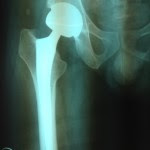

In June 2009, I underwent a ceramic bearing hip replacement. Recovery from surgery was surprisingly smooth. I had very little discomfort. I went through a rigorous rehab program under my surgeon’s supervision. His encouragement and my wife’s support helped me recover quickly.